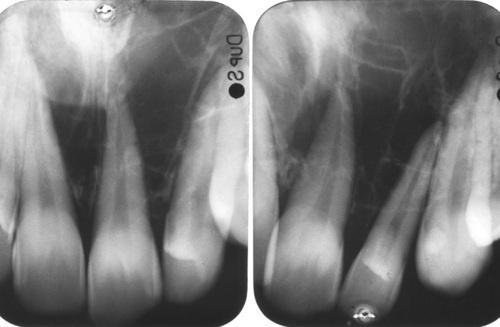

ameloblastoma

Periapical films of a smaller multilocular lesion, showing a “honeycombed” appearance.

Destructive radiolucent lesion with root resorption of the associated posterior teeth.